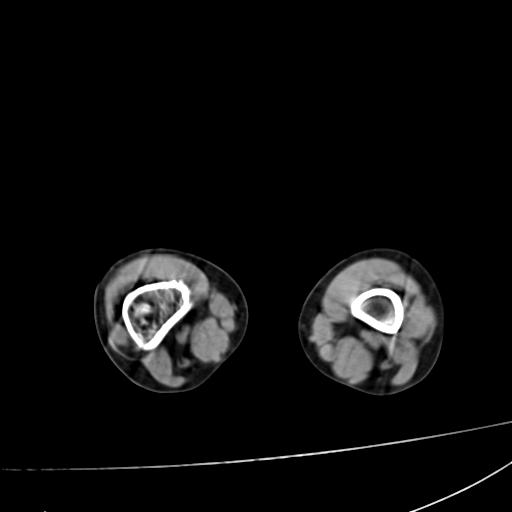

标题: PED0940:M12Y,左股骨下端酸痛畸形 [打印本页]

标题: PED0940:M12Y,左股骨下端酸痛畸形

12岁男孩,左膝关节肿痛8年,近月明显

内生骨软骨瘤?

血友性关节病?